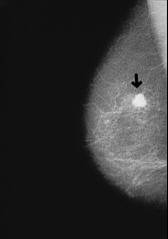

Beispiel: Röntgenbild bei Oberlappenpneumonie mit Verschattung im mittleren bis oberen Lungenbezirk rechts.

-- Brustkrebs, Röntgenfoto: http://www.prof-obwegeser.at/brustkrebs.htm

-- Lungenentzündung (Pneumonie), Röntgenfoto: http://www.doktor.com/krankheiten/lungenentzuendung.html